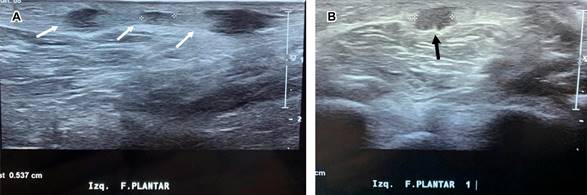

Femenino de 56 años, con índice de masa corporal de 21; practicante de pilates desde hace 10 años, acude por haber palpado en región plantar izquierda presencia de masa de 1 cm de diámetro; a la exploración dirigida: marcha normal, a la palpación tres nódulos palpables, no desplazables sobre planos profundos, discretamente dolorosas a la presión, de tamaños distintos (el mayor de 1 cm de diámetro y los otros dos de 0.5 cm). El mayor se encuentra localizado a la altura del escafoides. Con la sospecha clínica de fibromatosis plantar se efectúa ultrasonido, confirmando diagnóstico (Figura 1). Se derivó a rehabilitación, aplicando termoterapia y estiramiento de la fascia plantar; a tres meses de evolución, el nódulo mayor disminuyó a 0.5 cm de diámetro, no siendo palpables los dos más pequeños descritos al inicio.

La fibromatosis plantar, descrita por Ledderhose en 1897, implica la sustitución de la aponeurosis plantar por tejido fibroso; forma parte de las fibromatosis superficiales junto a la fibromatosis palmar o enfermedad de Dupuytren, la fibromatosis peneana o enfermedad de Peyronie y la de los cojinetes cutáneos o almohadillas de los nudillos. Habitualmente afecta un solo pie, pudiendo ser bilateral.2 Se desconoce su etiología, existiendo asociación con traumatismos repetitivos, diabetes mellitus, enfermedad hepática secundaria a alcoholismo y tabaquismo. El diagnóstico es clínico ante presencia de nódulos plantares, indoloras con sensación de cuerpo extraño en el apoyo plantar, de manera usual son localizadas en el arco longitudinal medial. La ultrasonografía, con frecuencia, es confirmatoria. La resonancia magnética es el estudio más eficiente y brinda información preoperatoria muy importante.3 El tratamiento inicial incluye: antiinflamatorios, modificación de las actividades tanto laborales como recreativas, inyección de corticosteroides o colagenasa4 en la lesión, uso de plantillas y terapia física con termoterapia y estiramiento de la fascia plantar. El manejo quirúrgico se indica cuando hay dolor y/o invasión de estructuras neurovasculares.